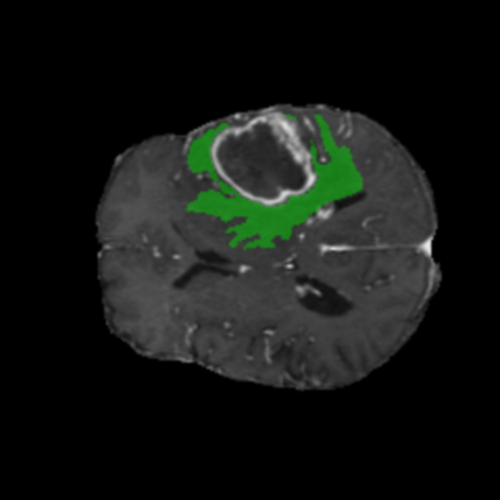

Ejemplos de Modalidades MRI

Visualización de las 4 modalidades de resonancia magnética y las segmentaciones de zonas tumorales utilizadas para entrenar el modelo

Glioma de Alto Grado (HGG)

Núcleo HGG

Núcleo

Edema HGG

Edema

Realce HGG

Realce

Tumor Completo HGG

Tumor Completo

Núcleo Edema Realce

🎯 Zonas Tumorales Segmentadas

• Núcleo (NCR): Región central no viable y necrótica del tumor

• Edema (ED): Inflamación (acumulación de líquido) en tejido cerebral sano circundante

• Realce (ET): Parte activa y viable del tumor, identificada por captación del contraste en T1ce